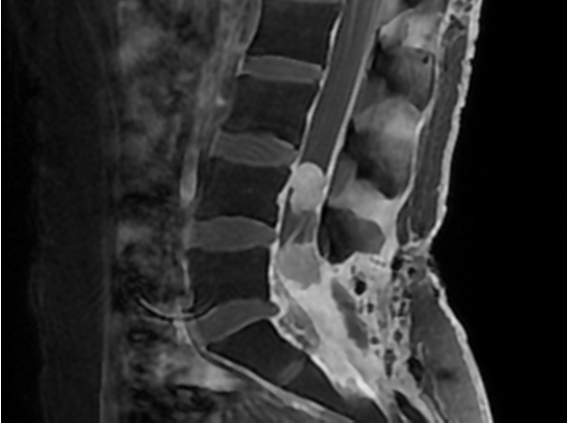

女性,25岁。右鼻腔鼻窦粘液表皮样癌术后、放疗后,脑转移术后放疗后,腰骶椎管内转移多次手术、放化疗后,右踝关节无力、脚底麻木1月余。当地医院行MRI检查示L4-5水平新发占位。我院复查腰椎MRI,提示肿瘤较前(1月前)明显增大。治疗方案:再次手术减压+术后药物治疗。术后病理提示:低分化粘液表皮样癌,伴生殖细胞肿瘤分化。药物治疗4周期见肿瘤显著缩小。图123治疗前,图4564周期药物治疗后。